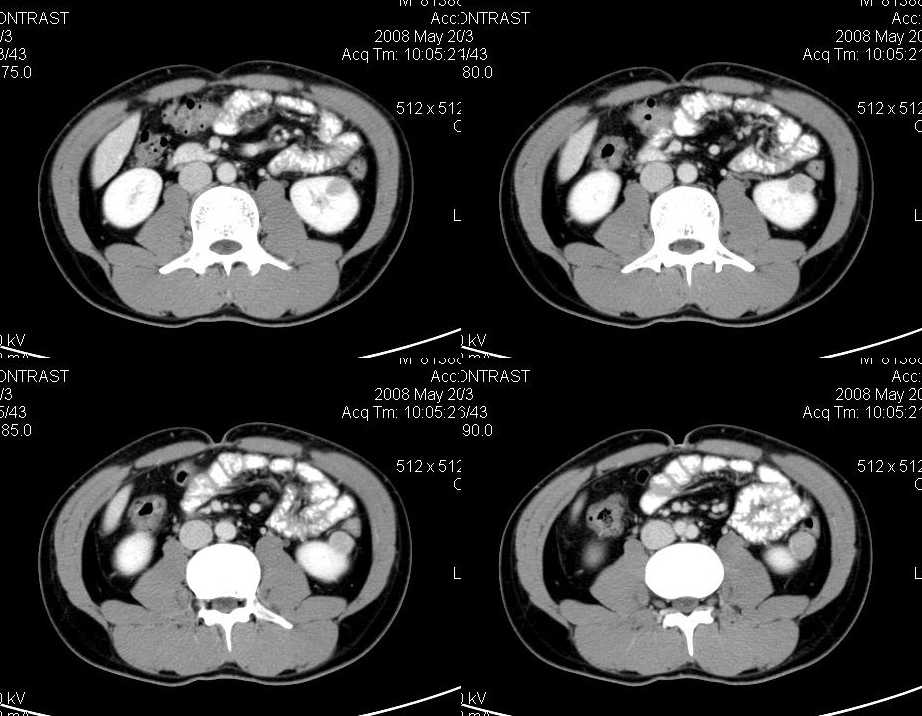

以下是引用liuyue在2008-6-7 15:28:00的发言:[br]典型的:肾癌。[br]动脉期强化明显,而静脉期密度明显降低,呈低密度。